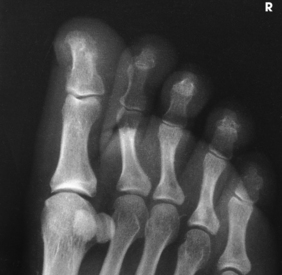

Radiographs may be obtained by directing the central ray perpendicular to the plane of the IR or by angling the central ray 10 degrees posteriorly. When a 10-degree posterior angle is used, the central ray is perpendicular to the metatarsals, reducing foreshortening. The TMT joint spaces of the midfoot are also better shown (Figs. 6-39 and 6-40).

Structures shown: The resulting image shows an AP (dorsoplantar) projection of the tarsals anterior to the talus, metatarsals, and phalanges (Figs. 6-43 to 6-45). This projection is used for localizing foreign bodies, determining the location of fragments in fractures of the metatarsals and anterior tarsals, and performing general surveys of the bones of the foot.

NOTE: The medial oblique is preferred over the lateral oblique because the plane through the metatarsals is more parallel to the IR, and it opens the lateral side joints of the midfoot and hindfoot better.

• Place the IR under the patient’s foot, parallel with its long axis, and center it to the midline of the foot at the level of the base of the third metatarsal.

• Rotate the patient’s leg medially until the plantar surface of the foot forms an angle of 30 degrees to the plane of the IR (Fig. 6-46). If the angle of the foot is increased more than 30 degrees, the lateral cuneiform tends to be thrown over the other cuneiforms.1

Structures shown: The resulting image shows the interspaces between the following: the cuboid and the calcaneus, the cuboid and the fourth and fifth metatarsals, the cuboid and the lateral cuneiform, and the talus and the navicular bone. The cuboid is shown in profile. The sinus tarsi is also well shown (Fig. 6-47).

• Rotate the leg laterally until the plantar surface of the foot forms an angle of 30 degrees to the IR.

• Support the elevated side of the foot on a 30-degree foam wedge to ensure consistent results (Fig. 6-48).

Structures shown: The resulting image shows the interspaces between the first and second metatarsals and between the medial and intermediate cuneiforms (Fig. 6-49).